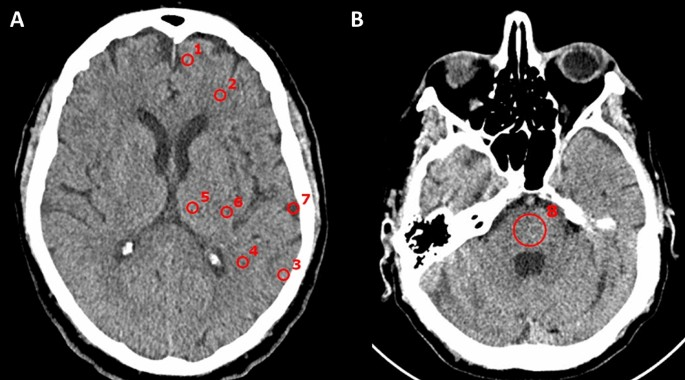

Computed Tomography (CT)

uses X-rays to create detailed cross-sectional images of the brain.

often used to identify structural abnormalities such as tumors or bleeding